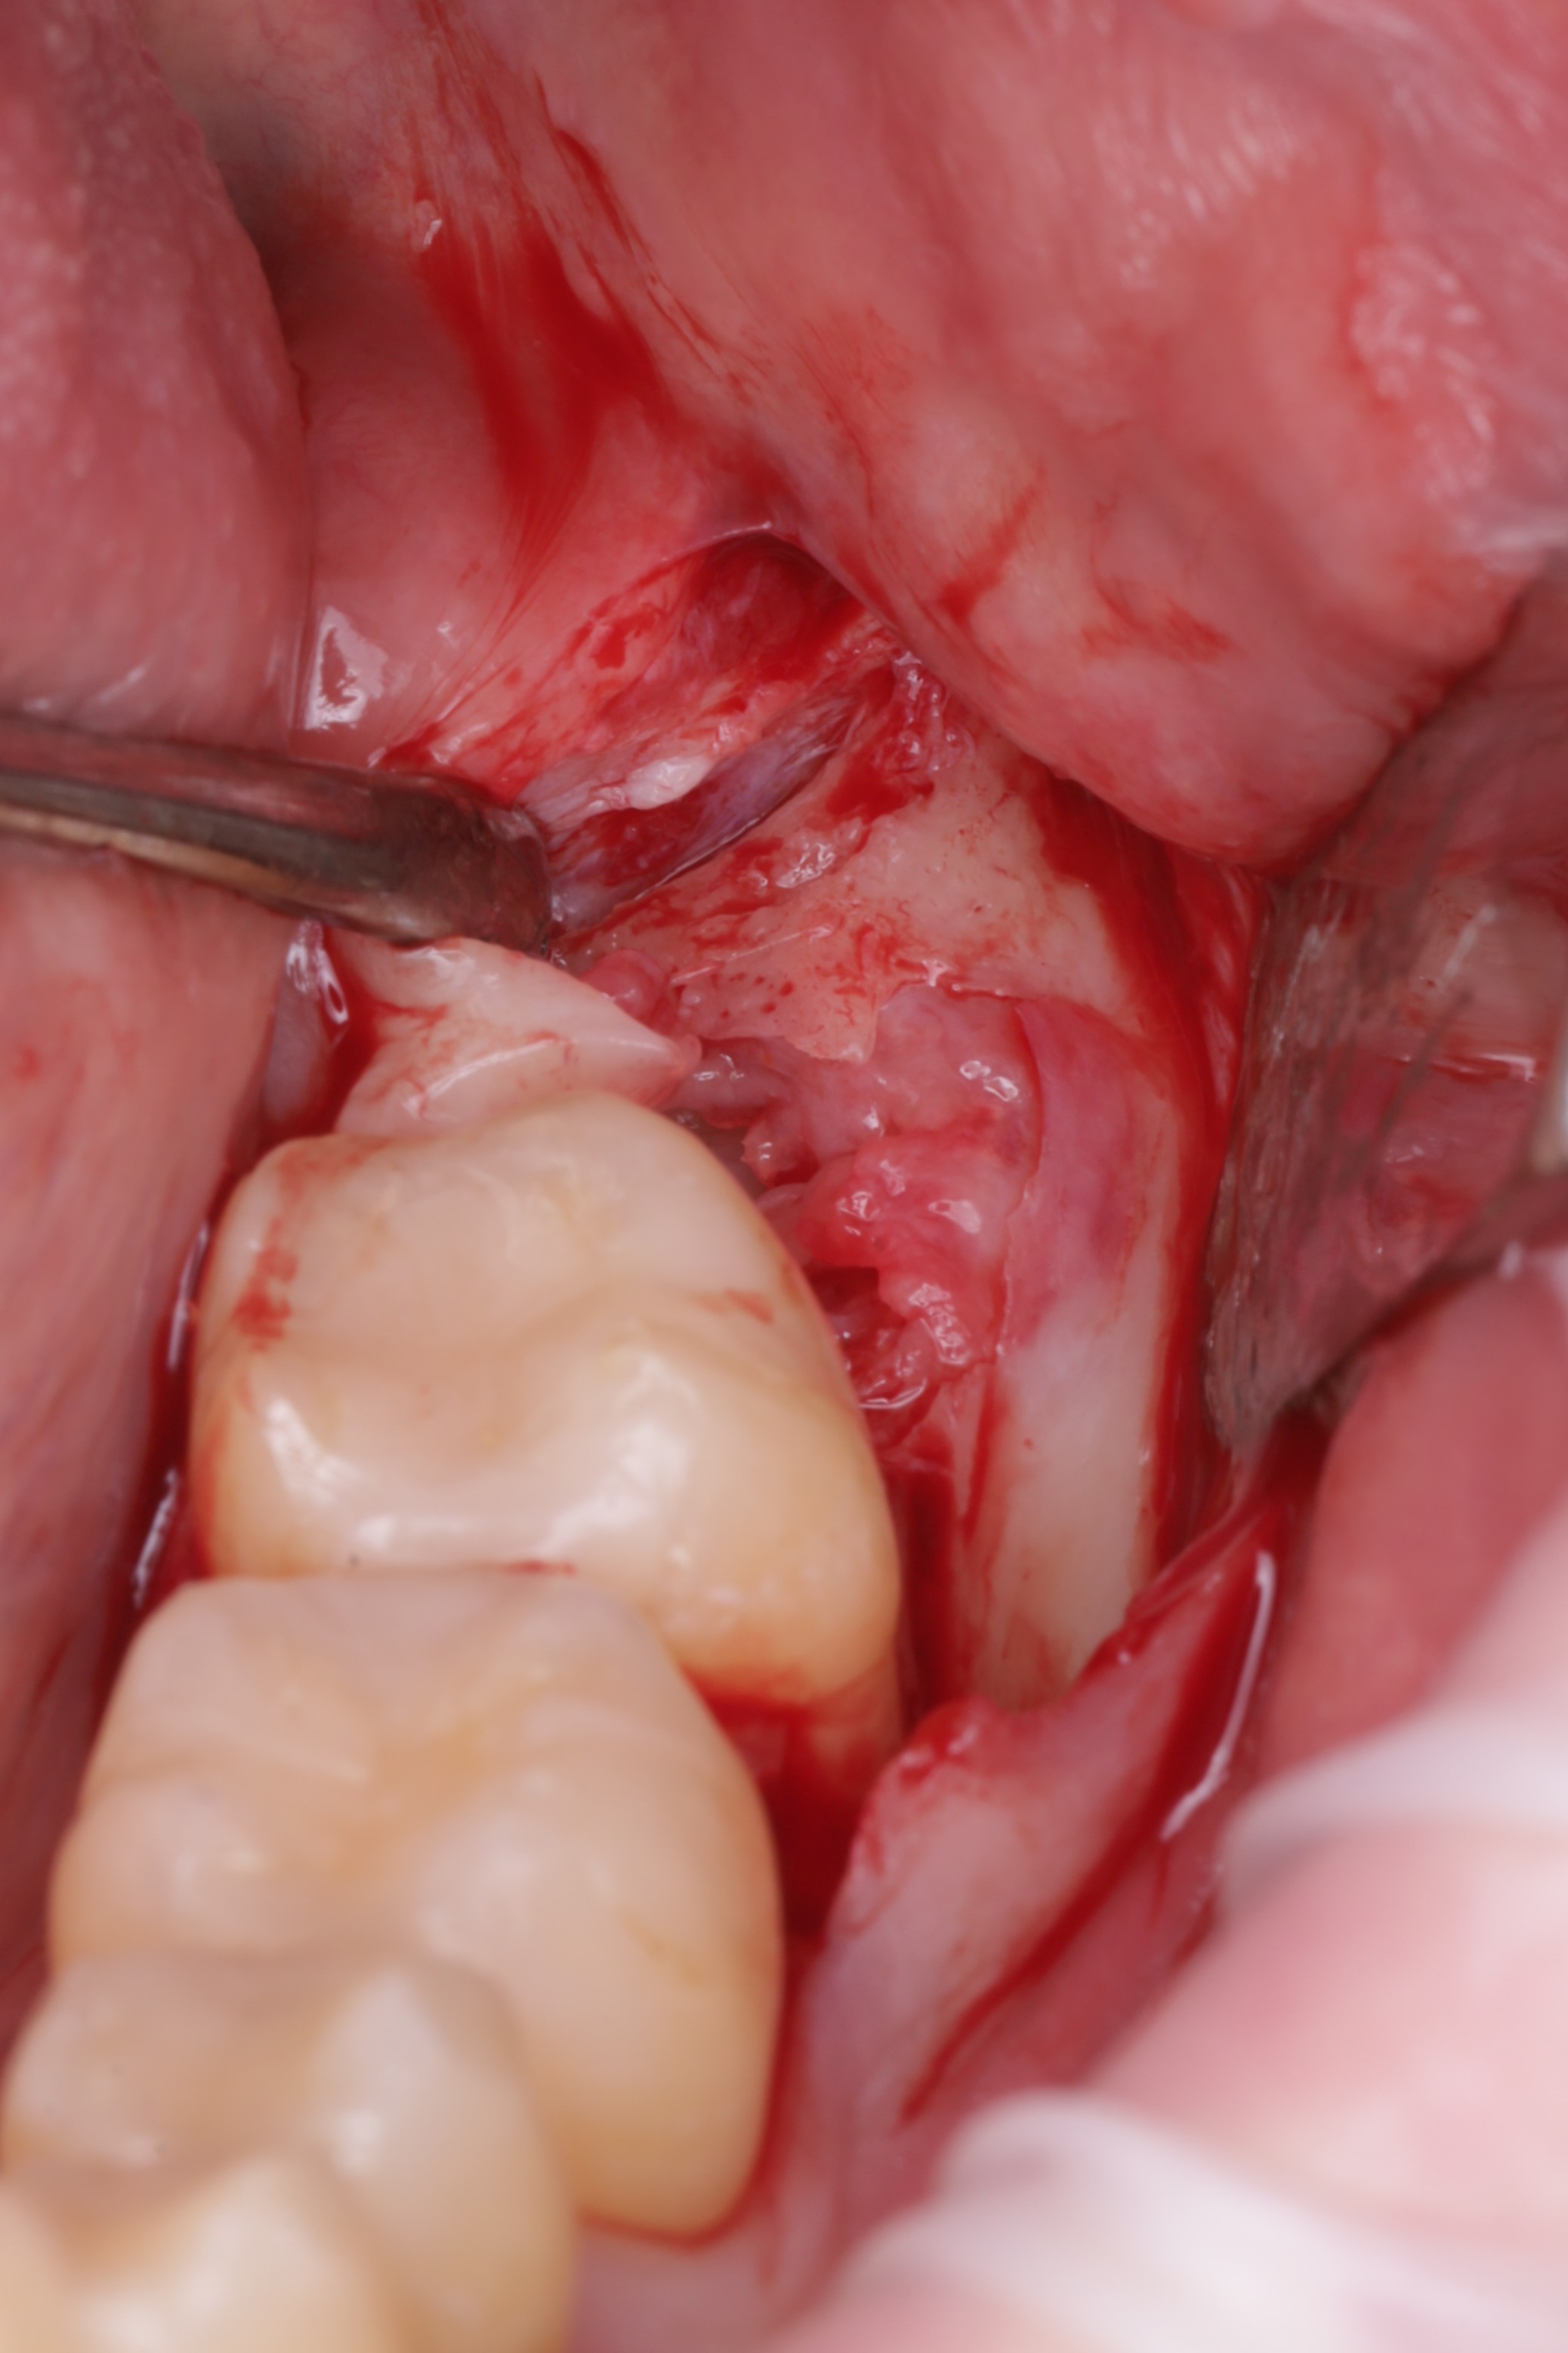

Аккуратно сформирован доступ к ретинированному зубу

Произведено иссечение тканей коронковой части зуба

Раскрытие раны и снятие ортодонтических тяг